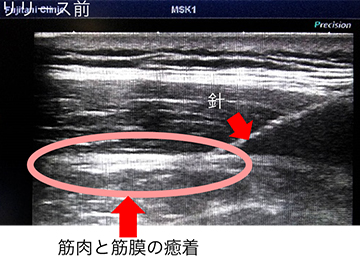

筋膜リリースとは(保険適応外)

Fascia(ファシア)と呼ばれる組織を包む膜の表面に出現する発痛源を注射などで治療する方法を、Fasciaリリース(筋膜リリース)と呼びます。 筋肉を包むFasciaには多くの知覚神経が存在しており、肩こりや慢性腰痛の患者様の筋外膜間には多くの疼痛物質の存在やヒアルロン酸の粘度の上昇が報告されています。 超音波をあてながらこのFasciaと筋肉の間に薬液を注入しリリース(開放)することで、局所補液効果による鎮痛効果(疼痛物質の洗い流し)と、 Fascia同士の摩擦(ストレス)の改善から組織の滑走性や可動性、伸張性の向上が得られると考えられています。副作用の心配はほとんどなく、治療直後からの鎮痛・徐痛が期待されます。

筋膜リリースの画像 筋膜リリースの画像 筋膜リリースの画像